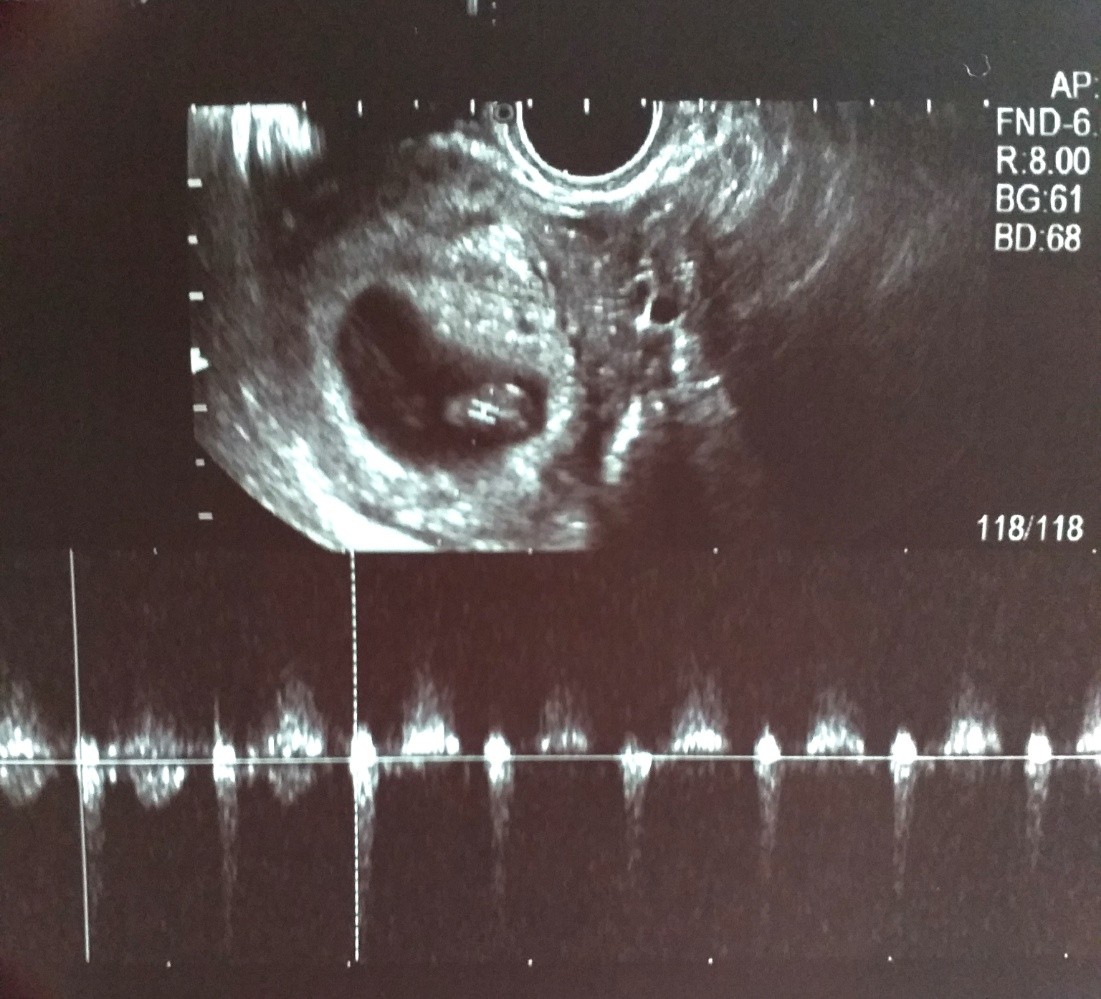

Przepraszam że namieszalam z tą tajną gupą a sama przy trójce czasem znikam na dłużej. Byłam dzisiaj na badaniu. Wszystko dobrze. 8 tydz i 2 dni. Ale zdjęcia słabe, też chciałam mieć takiego "miśka haribo" a nic prawie nie widać. Tyle kasy bo musialam iść prywatnie a miśka nie widać. Na ekranie nawet był ale nie uchwyciła.